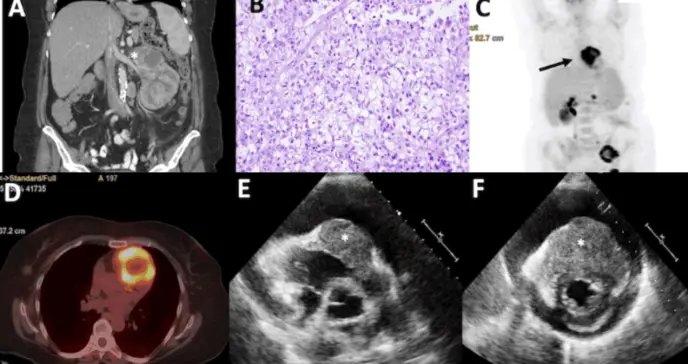

La tomografía axial computarizada (TAC) evidenció una masa renal izquierda de gran tamaño con infiltración de estructuras linfáticas y vasculares adyacentes. Ante la alta sospecha de neoplasia, se procedió a realizar una nefrectomía radical, confirmándose posteriormente el diagnóstico histológico de carcinoma renal de células claras.

El estudio de extensión mediante PET-TAC mostró una diseminación metastásica generalizada, incluyendo una hipercaptación a nivel cardíaco, altamente sugestiva de metástasis.

Dada la inestabilidad hemodinámica, se realizó un ecocardiograma transtorácico urgente, que reveló un derrame pericárdico grave y un engrosamiento infiltrativo del septo interventricular, el ápex y el tracto de salida del ventrículo derecho.

Estos hallazgos sugerían compromiso cardíaco por metástasis, con desarrollo de taponamiento cardíaco.